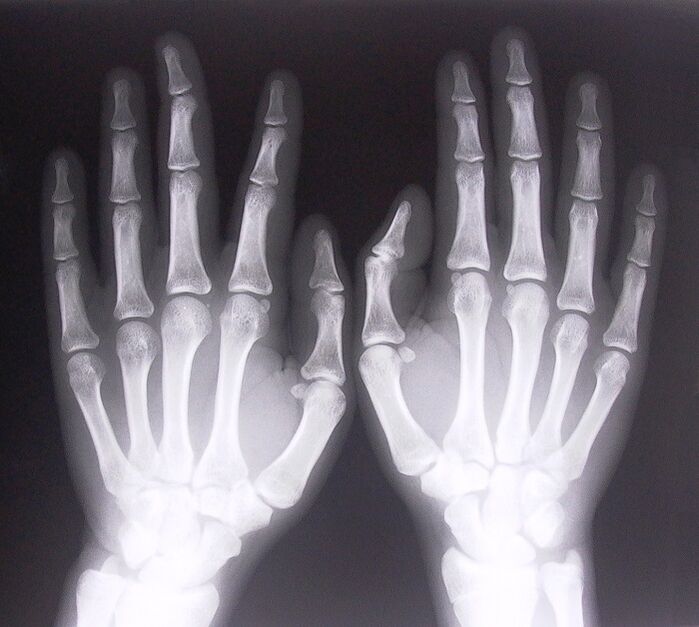

- Stenosierende Ligamentitis. Um die Ursache der Erkrankung zu ermitteln, ist eine Röntgenaufnahme erforderlich. Die Symptome sind typisch: schmerzhafte Bewegung der Hand, Schlingen der geballten Handfläche. Außerdem sind beim Ausfahren meist Klickgeräusche zu hören.

- Machen Sie Röntgenaufnahmen.